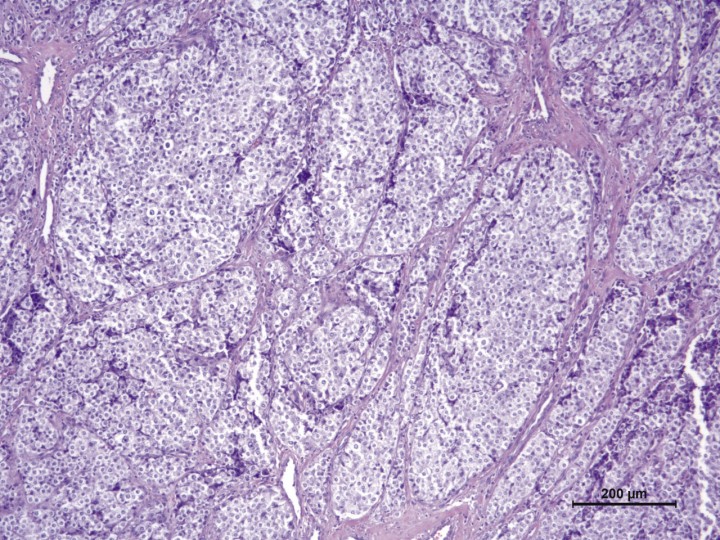

La masa extraída es sometida a estudio histopatológico con el fin de poder emitir un diagnóstico definitivo. Macroscópicamente se trata de una masa de 3 x 4 cm (Fig. 5), polilobulada, de consistencia firme que, a la sección, muestra áreas blanquecinas y otras más oscuras. El estudio histológico revela una proliferación neoplásica multilobular parcialmente encapsulada, con áreas multifocales de invasión capsular, compuesta por paquetes de células separados por abundante estroma fibroso con presencia de numerosos vasos sanguíneos y nervios. Las células neoplásicas presentan un citoplasma pálido granular y un núcleo redondo central. El grado de atipia celular es moderado, observándose ocasionales células multinucleadas (Fig. 6). De forma puntual, se observan células neoplásicas en luces vasculares. Las células neoplásicas alcanzan todos los márgenes de resección quirúrgicos.

<p>Tinción de hematoxilina-eosina en la cual se aprecian paquetes compactos de células neoplásicas separados por trabéculas de tejido fibroconjuntivo. Las células neoplásicas tienen una forma de redonda a poliédrica y un citoplasma pálido granular. 100x.</p>

Figura 6

Tinción de hematoxilina-eosina en la cual se aprecian paquetes compactos de células neoplásicas separados por trabéculas de tejido fibroconjuntivo. Las células neoplásicas tienen una forma de redonda a poliédrica y un citoplasma pálido granular. 100x.